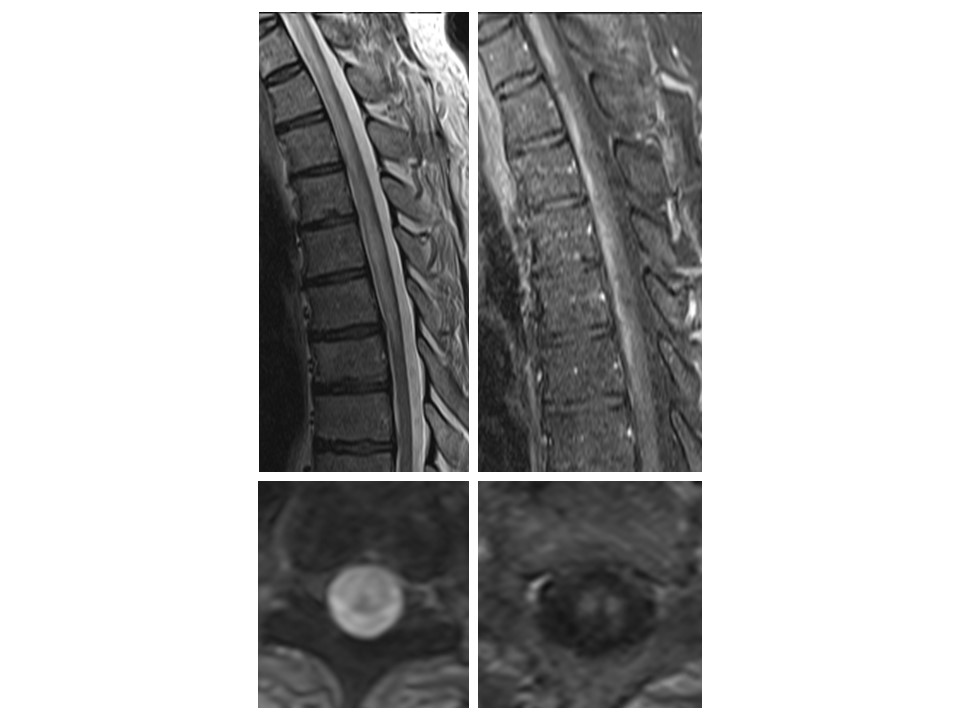

▶️Recognize key imaging findings (pencil, owl eyes)